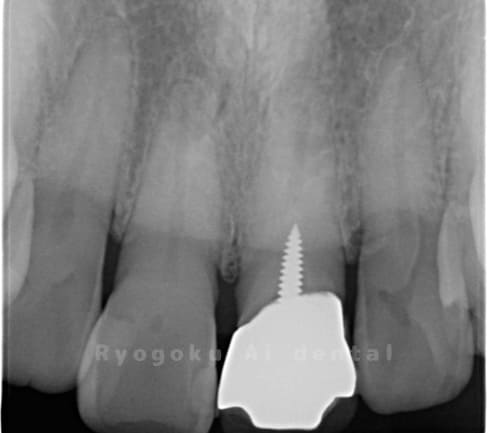

Case11

-

- 原因

- 慢性根尖性歯周炎

- 治療内容

- マイクロエンド

- 治療費用

- 77,000円(被せ物は含まない)

前歯が痛いとのことでご来院された患者様です。マイクロスコープ、MTAを用いて、緊密に根管充填を行い、現在、痛みもなく経過は良好です。

<リスク・副作用>

術後は痛み、腫れ、痺れなどの副作用が生じる場合があります。症状が再発する可能性があります。